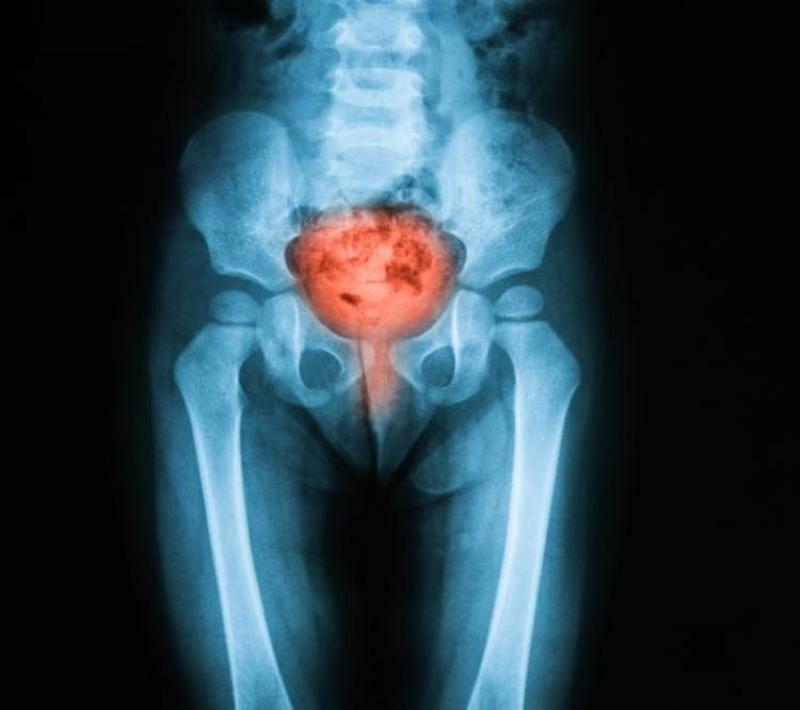

What is Bladder Cancer?

Bladder cancer occurs in the same way that other cancers occur - which is when cells in an organ in your body don't grow or behave in the pattern that they are supposed to. Once cells begin to do this, they multiple, making for a tumorous tissue.

About 90% of all bladder cancers begin in the urothelium, which is the tissue that lines the inside of the bladder, ureters, urethra, and renal pelvis. This type of bladder cancer is the most common and is medically called urothelial carcinoma.